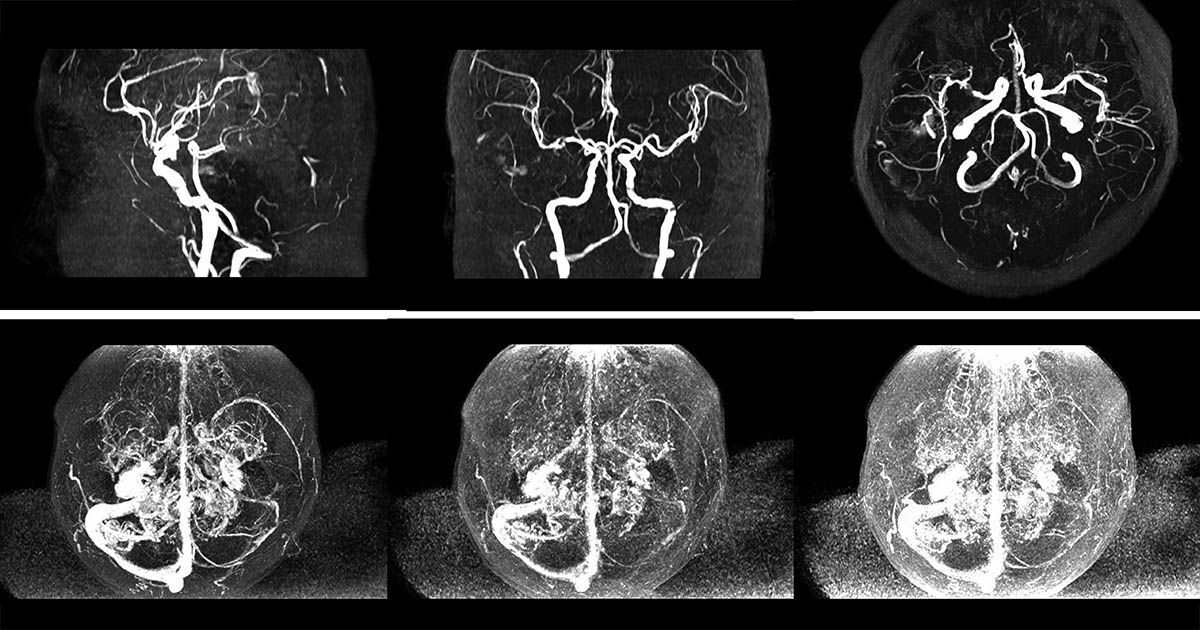

El ictus, también se conoce como accidente cerebrovascular, infarto cerebral o derrame cerebral. Se trata del síntoma o conjunto de síntomas que aparecen como consecuencia de la interrupción del aporte de flujo sanguíneo a una parte del cerebro.

Así, explica que los síntomas de ictus pueden presentarse tanto cuando un trombo obstruye la circulación de una arteria en el cerebro (85% de los casos), como cuando una arteria se rompe y la sangre arterial se vierte al interior del cerebro (15% de los casos).